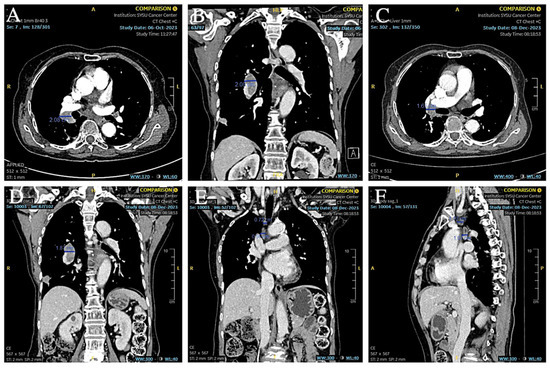

From the end of the surgery to 2021-12-27 (12 months postoperatively), no abnormalities were found in the review imaging and no prophylactic treatment was performed. On 20 June 2022 (18 months postoperatively) when the CT was reviewed again, it was found that the right hilar lymph node was significantly enlarged compared to the previous one, with the short diameter increasing to about 14mm and with obvious enhancement, but still no corresponding treatment was performed (Figure 7A,B). During the period July 2022 to June 2023 (12 months), the patient’s CT results suggested that the lymph nodes were stable, and did not progress again until September 2023, and the patient refused treatment during this period. On 4 September 2023 (33 months after the operation), the CT examination was repeated and found that the multiple enlarged lymph nodes in both hilar regions had partially fused with each other, and the short diameter had increased to about 21 mm, with unclear boundaries and uneven enhancement, which was considered to have a high possibility of metastasis (Figure 7C–F). The patient was suspected of having recurrent metastases in the right hilar lymph nodes, so the patient received an ultrasonic bronchoscopic puncture biopsy (EBUS-TBNA), and the results of the biopsy showed that heterogeneous cells were seen in the right hilar lymph node fluid matrix and cell block sections, and the morphology was consistent with malignant tumor cells, which were suspected to be small cell carcinoma cells. Immunohistochemical results: ALK(D5F3) (+); ALK-N (−); CK(AE1/AE3) (+); TTF-1 (+); CD56 (+); Syn (+); CgA (+); and Ki-67 (about 80%+) (Figure 8). Immunohistochemistry results still showed no non-small cell histologic binding. Combined with the history and immunohistochemical results, this was consistent with small cell carcinoma relapse.

Figure 7. (A,B) CT showed that the short diameter of the right hilar lymph node had increased to 14 mm. (CF) CT showed that the right hilar lymph node continued to increase in size and the short diameter increased to 21 mm.